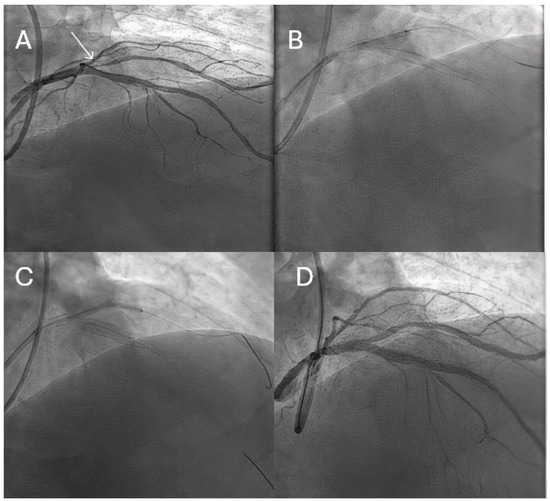

- Pellegrini, D.; Donahue, M.; Regazzoli, D.; Tedeschi, D.; Loffi, M.; Pellicano, M.; De Blasio, G.; Tespili, M.; Guagliumi, G.; Ielasi, A.; et al. Drug-coated balloon combined with drug-eluting stent for the treatment of coronary bifurcation lesions: Insights from the HYPER study. Eur. Heart J. Suppl. 2023, 25, C79–C83. [Google Scholar] [CrossRef] [PubMed]

- Corballis, N.H.; Paddock, S.; Gunawardena, T.; Merinopoulos, I.; Vassiliou, V.S.; Eccleshall, S.C. Drug coated balloons for coronary artery bifurcation lesions: A systematic review and focused meta-analysis. PLoS ONE 2021, 16, e0251986. [Google Scholar] [CrossRef]

- Ke, D.; He, X.; Chen, C.; Lin, C.; Luo, Y.; Fan, L.; Li, S.; Zheng, X.; Chen, L. Randomized Pilot Study to Compare DCB-Based versus DST-Based Strategies for the Treatment of True or Complex Coronary Bifurcation Lesions. Rev. Cardiovasc. Med. 2023, 24, 99. [Google Scholar] [CrossRef]

- Kleber, F.X.; Rittger, H.; Ludwig, J.; Schulz, A.; Mathey, D.G.; Boxberger, M.; Degenhardt, R.; Scheller, B.; Strasser, R.H. Drug eluting balloons as stand alone procedure for coronary bifurcational lesions: Results of the randomized multicenter PEPCAD-BIF trial. Clin. Res. Cardiol. 2016, 105, 613–621. [Google Scholar] [CrossRef]